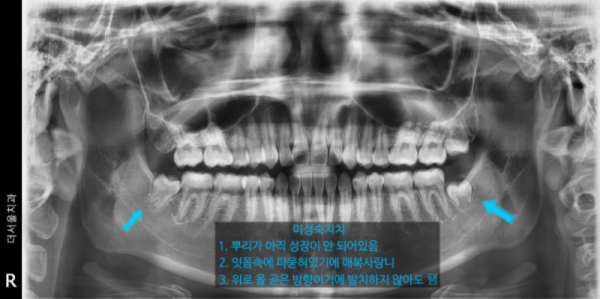

7c2dca8d93c24486ebc701a49e70bb3e_1645368651_5066.png

사랑니는 반드시 발치해야 한다고 볼 수는 없습니다.

사랑니의 모양이 정상적이거나

사랑니의 맹출된 위치가 정상적이거나

정상적으로 잘 양치질이되어 관리가된다면

사랑니는 뽑지 않아도 괜찮습니다.